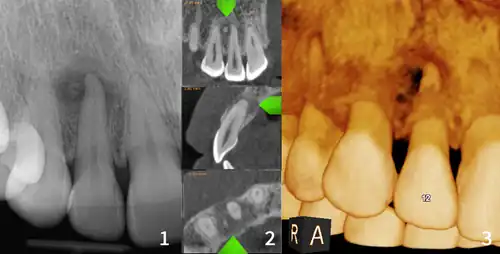

| Florid osseous dysplasia of the mandible | |

| Diagnostic method | X-ray, CBCT scan, vitality testing of teeth |

Diagnosis is based on clinical and radiographic observations, and in rare cases, biopsy may be performed.[3] Diagnosis is important so that the treating doctor does not confuse it for another periapical disease such as rarefying osteitis or condensing osteitis. Incorrect diagnosis could lead to unnecessary root canal treatments, or biopsy or surgical intervention which can be invasive and increase the risk of infection.[5] A pulp vitality test such as a cold test or electric pulp test can aid in diagnosis, since COD generally does not compromise pulp vitality.[6] COD can be found in individuals of all ages and ethnic backgrounds, but it has been observed more frequently in individuals of African, East Asian, and Asian descent.[7] Cone-beam computed tomography (CBCT) has proven useful in distinguishing between COD and periapical cysts, when examined with quantitative texture analysis using specialized software.[5]